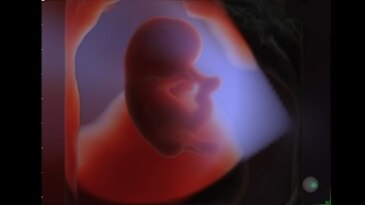

13-week fetal profile